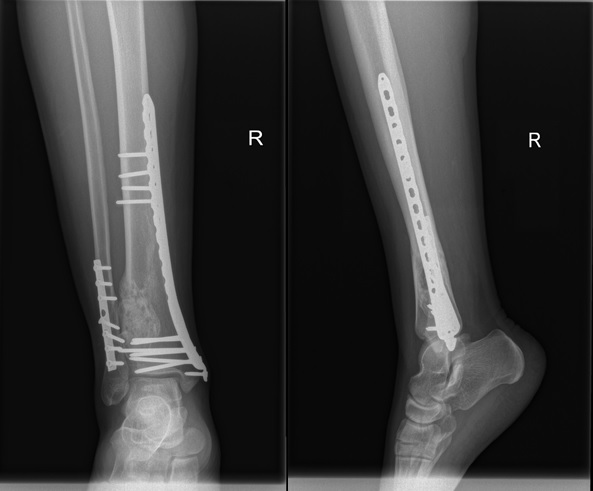

A 23-year-old healthy male presented to the accident & emergency department complaining of pain in the right lower leg and ankle following a trivial twisting injury to the right ankle while training in the gym. On examination, the patient had severe pain and mild swelling to the right lower leg and ankle with no visible deformity, normal skin condition and intact distal neurovascular status. Initial radiologic examination revealed a distal third tibia and fibula long oblique displaced fractures that were associated with a roughly 3cm x 2cm well-defined exapnsile, lobulated and lytic lesion with hypersclerotic margins and a narrow transitional zone (Figure 1). Routine laboratory investigations including a complete blood count, liver function test and renal function test did not reveal any abnormalities. An initial diagnosis of pathological fracture with a differential diagnosis of non-ossifying fibroma versus chondromyxoid fibroma was, therefore, made. The patient was, accordingly, planned for bone curettage and primary fixation of the distal tibia and fibula.

Figure 1 Initial injury AP and lateral x-rays - distal tibia and fibula fractures with an associated expansile, lobulated and lytic lesion with hypersclerotic borders.